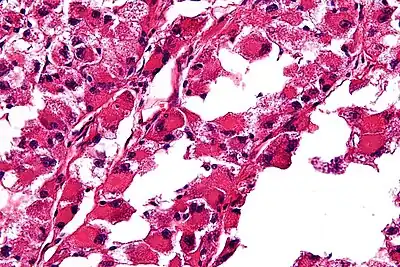

| Micrograph of an alveolar soft part sarcoma, showing the characteristic alveolar-like architecture and cells with eccentric nuclei and abundant eosinophilic cytoplasm. H&E stain. | |

ASPS' histomorphologic features include an alveolar-like pattern at low magnification and the presence of large cells with abundant eosinophilic cytoplasm and eccentric nuclei. Calcifications are commonly present, as may be seen with slow-growing neoplasms.

High-magnification micrograph showing the characteristic large cells with abundant eosinophilic, i.e. pink, cytoplasm and an eccentrically placed nucleus